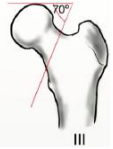

Pauwels III

> 70º

Riesgo de pseudo art / necro avasc